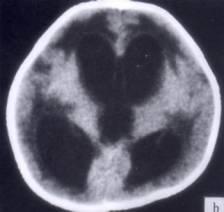

病历摘要:??患者女性,10岁。结核性脑膜炎愈后8月,头痛伴恶心呕吐1周,并渐加重。体检:神清,精神差,反应迟钝,双眼底视神经乳头水肿,双眼外展差,余未见...

问题 病历摘要:??患者女性,10岁。结核性脑膜炎愈后8月,头痛伴恶心呕吐1周,并渐加重。体检:神清,精神差,反应迟钝,双眼底视神经乳头水肿,双眼外展差,余未见明显异常。 目前治疗脑积水的措施包括下列哪些?